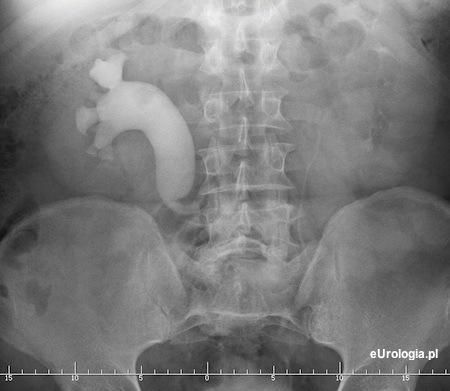

Moczowód poza żyłą główną dolną - łac. ureter retrocavalis - circumcavalis jest rzadką wadą prawego moczowodu polegającą na tym, że moczowód skręca przyśrodkowo i przebiega odcinkowo poza żyłą główną. Wodonercze u pacjenta z moczowodem położonym poza żyłą główną dolną jest wskazaniem do leczenia operacyjnego. Operacja polega na wypreparowaniu moczowodu i zespoleniu koniec do końca.

Fot. Zdjęcie urograficzne pacjenta z moczowodem retrokawalnym.